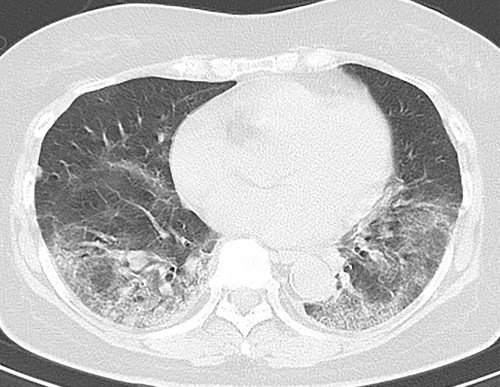

Коронавирус менен симптомдору жок ооругандардын өпкөсү жабыркаган